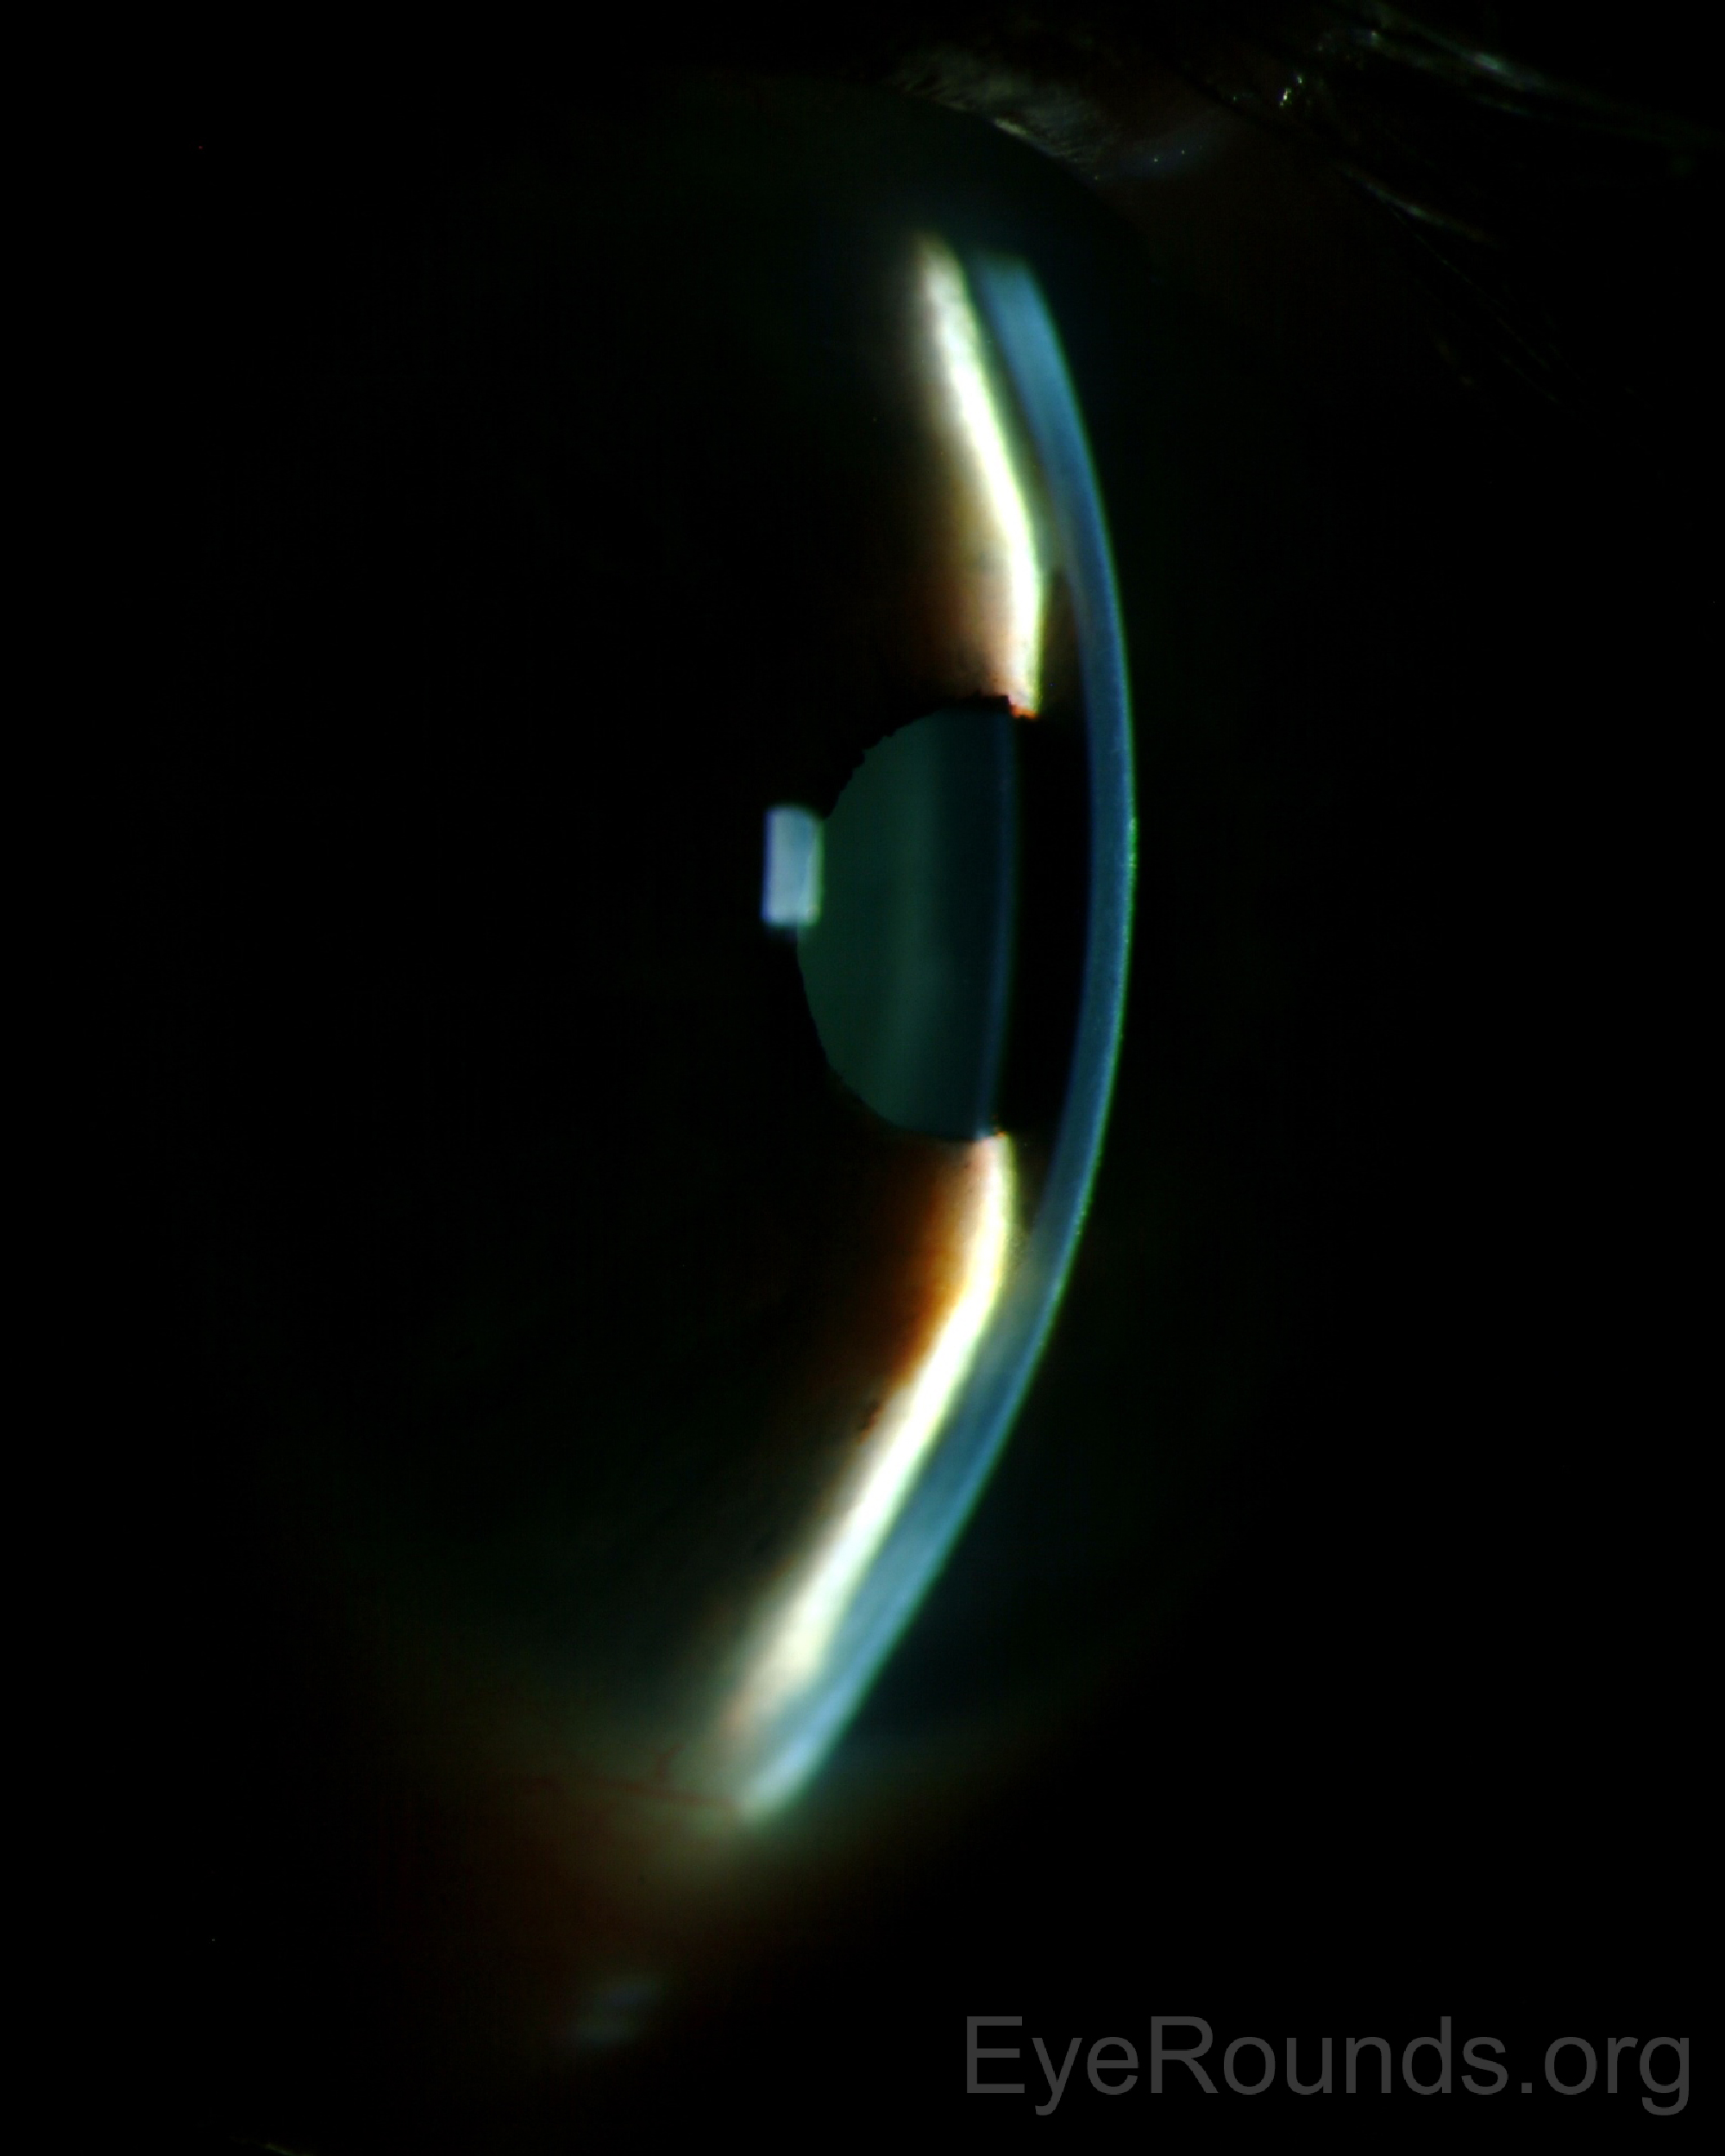

방수흐름이상 악성녹내장이 발생하게되면,

홍채절제술이 있음에도 불구하고, 높은 안압과,

전방의 중심부 및 주변부 모두가 얕아진 소견을 보입니다.